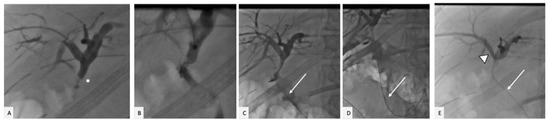

2. Case Presentation